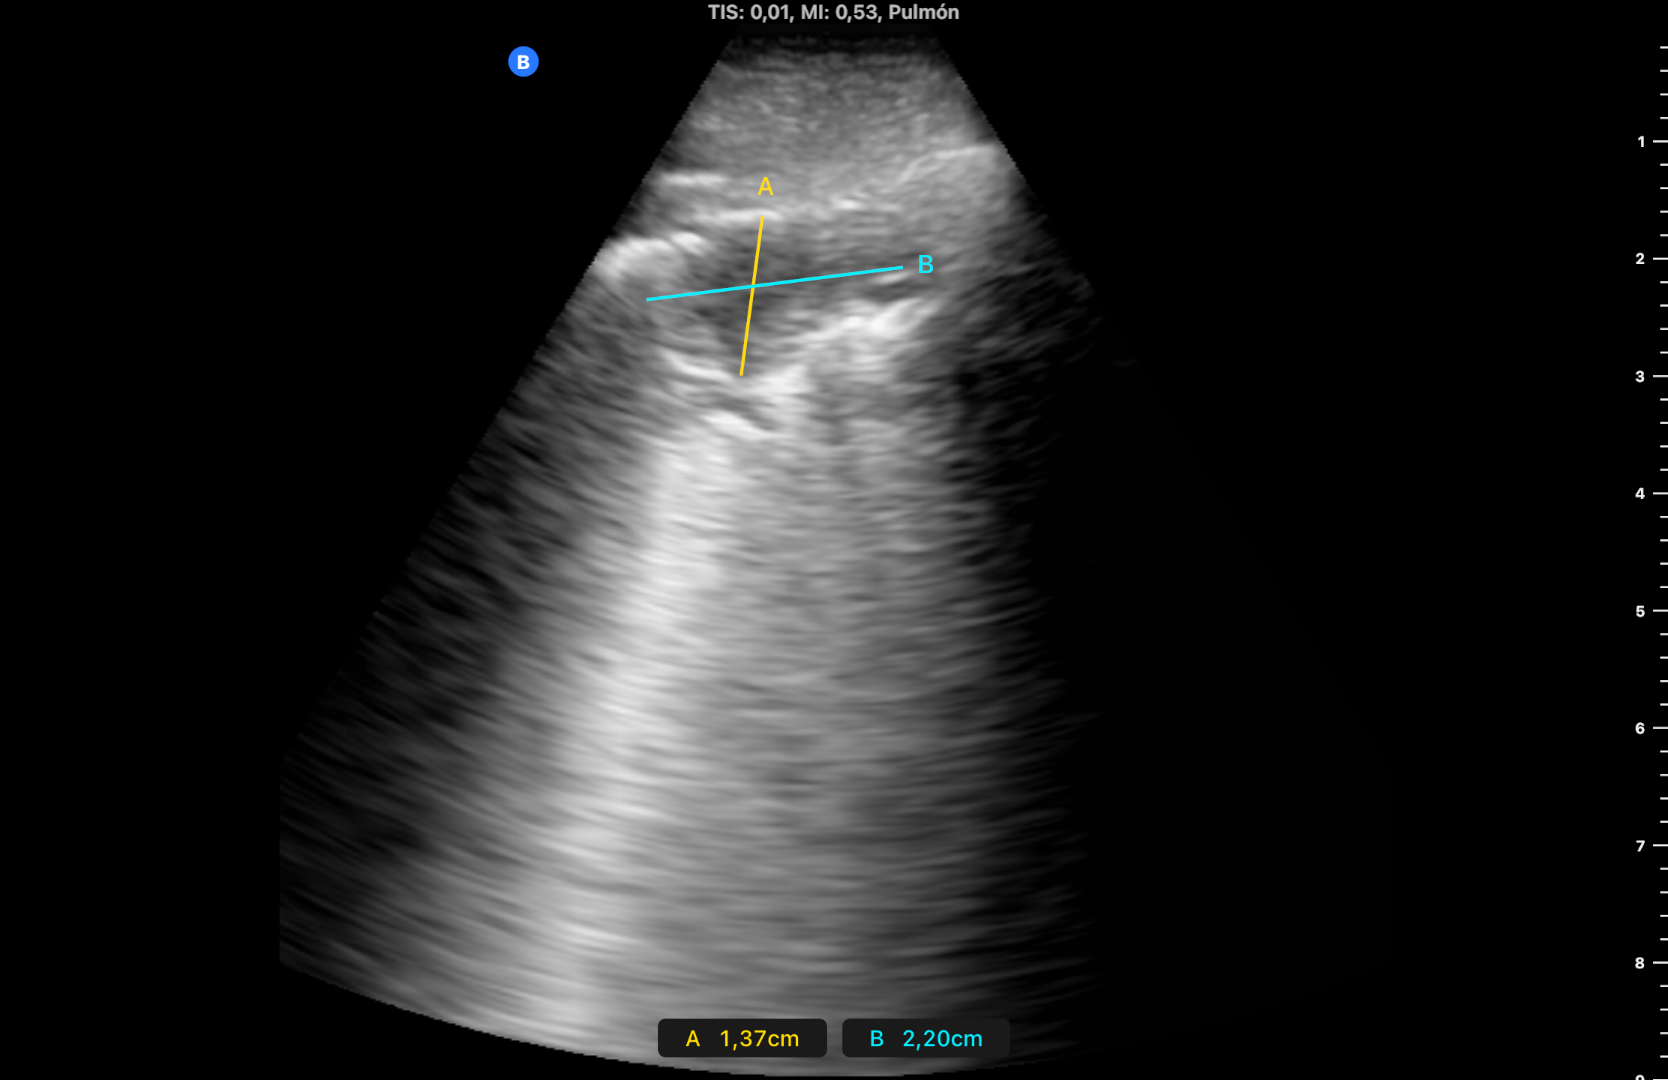

Visita al paciente a los 4 días, manteniendo buen estado general y afebril, con similar imagen ecográfica. Se vuelve a visitar a los 15 días, el paciente está asintomático y en la ecografía ha desaparecido el derrame pleural y la consolidación ha disminuido a 2 x 1,5 cm (imagen 3). A los 2 meses se realiza visita de seguimiento, con mejoría clínica y ecográfica con microconsolidación y líneas B aisladas, pero la familia refiere inflamación desde hace 10 días de la pierna derecha, por lo que se realiza nueva ecografía venosa de MID a nivel inguinal y poplíteo visualizando a este último nivel material ecogénico (imagen 4) y ausencia de compresión. Se inicia tratamiento con heparina a dosis terapéuticas, apoyando el diagnóstico una analítica en domicilio al día siguiente con dímero D de 3769.